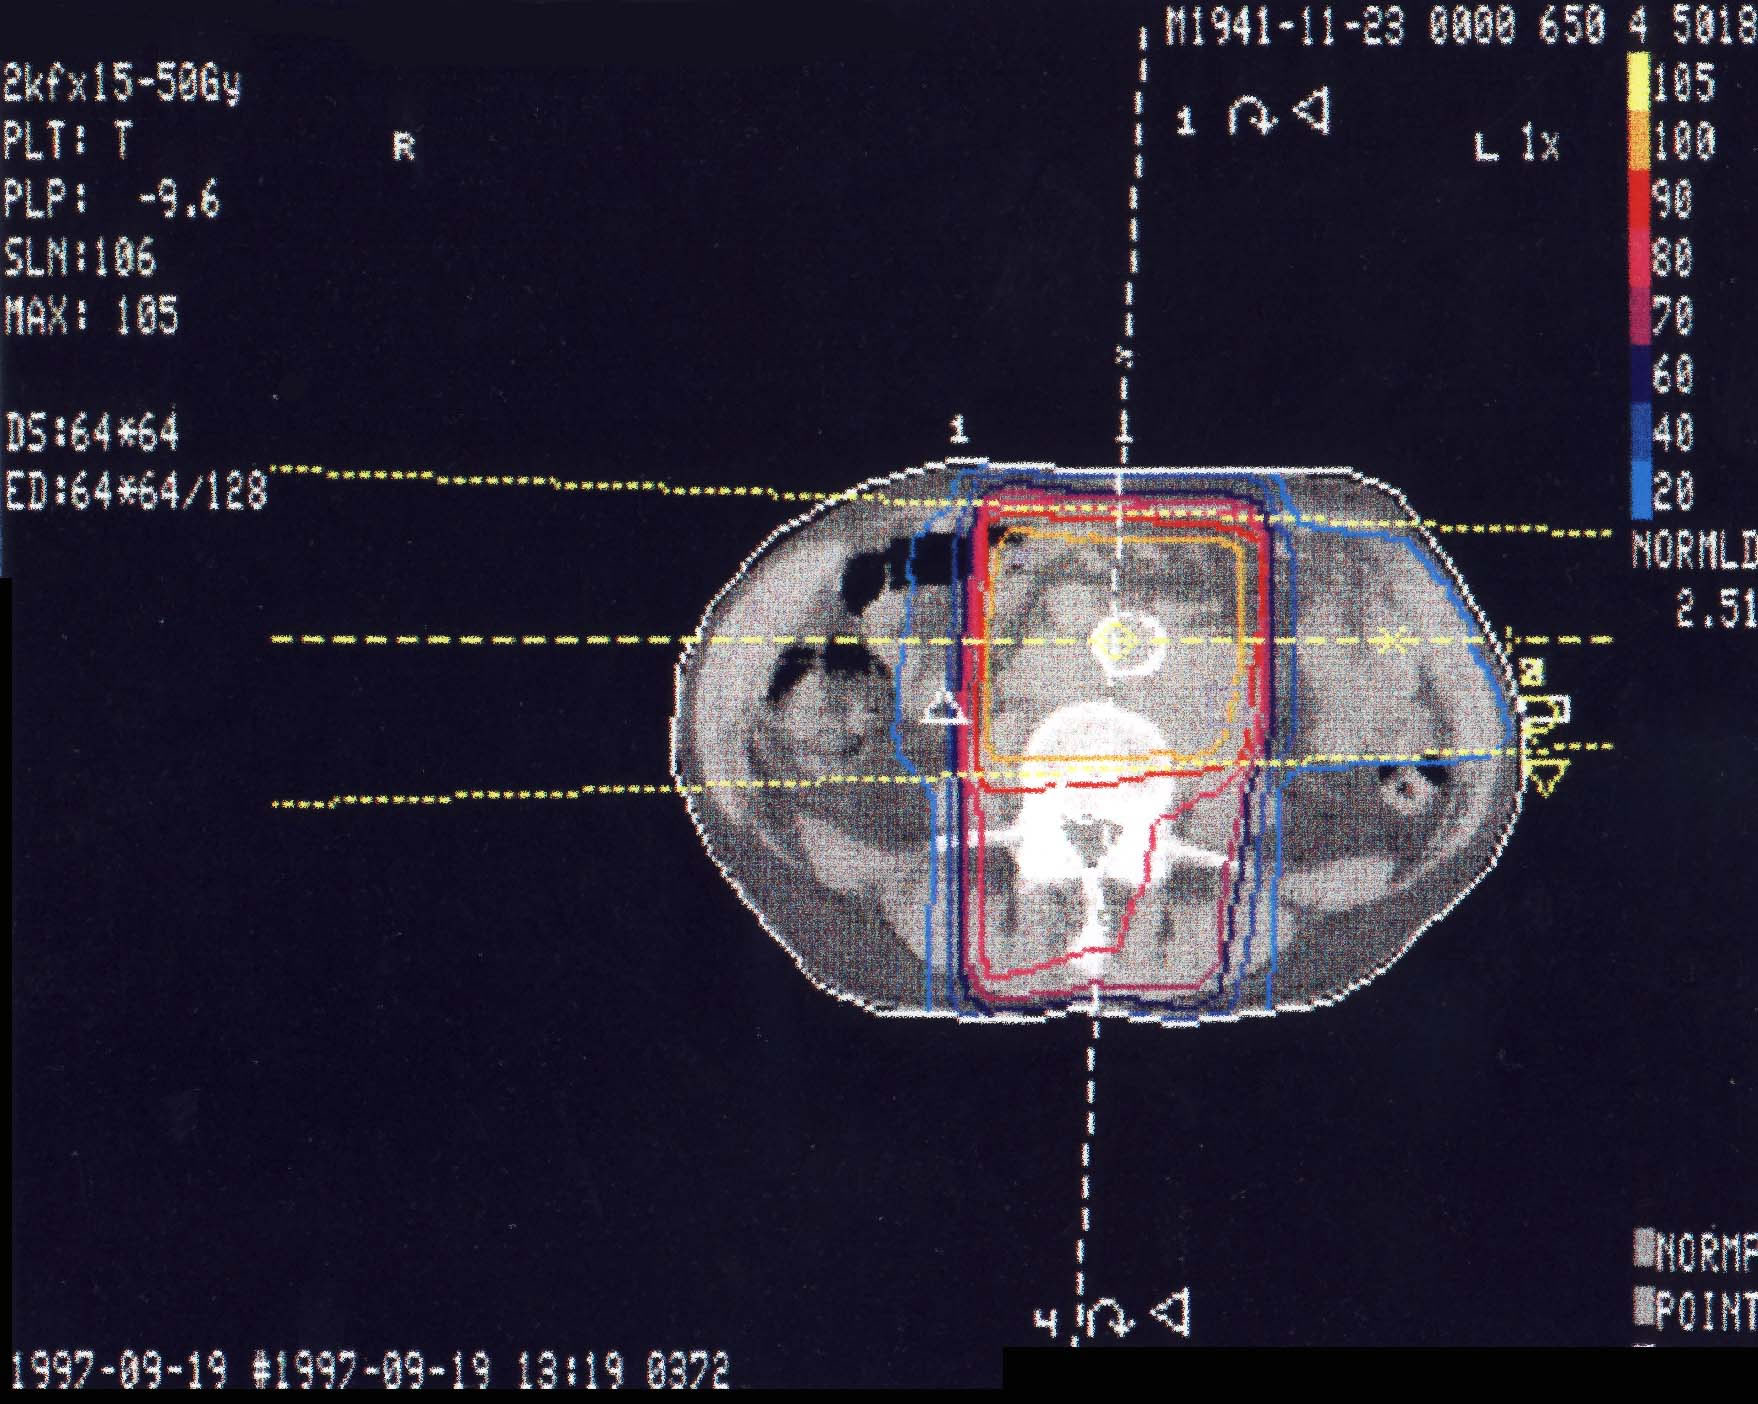

Lymphknotenmetastasen: Bestrahlungsplan

Einführung aktuelle Bilder - Einführung Bestrahlungspläne - Einführung Demonstration